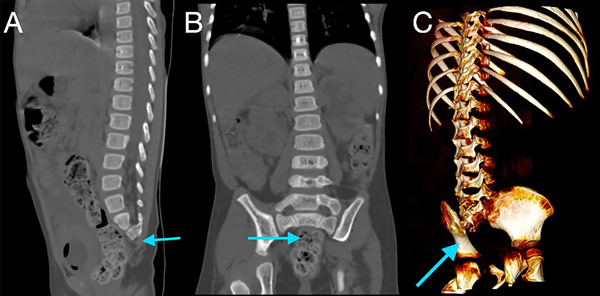

En la tomografía se evidenció presencia de S1-S2 con ausencia del resto de cuerpos sacro-coxígeos, así como hipodensidad a nivel de la médula que podría sugerir siringomielia (Figura 1). También se encontró falta de unión de algunos elementos posteriores a nivel de L5-S1 (Figura 2), lo que sugiere el diagnóstico de síndrome de regresión caudal asociado a probable siringomielia y probable vejiga neurogénica dado engrosamiento marcado de las paredes vesicales (Figura 3). Además, se encontró dilatación ureteropielocalicial de forma bilateral (Figura 4). A raíz de estos hallazgos, se solicitó una valoración por genética clínica, la cual determinó que la paciente cumple con los criterios clínicos de regresión caudal y tiene antecedentes de diabetes gestacional insulino-dependiente, lo cual es un factor de riesgo.

Figura 1. Tomografía de abdomen simple en ventana ósea, reconstrucciones sagital (A), coronal (B) y 3D (C), mostrando la presencia de vertebras sacras 1 y 2, con ausencia del restante de los elementos óseos sacro-coxígeos (flechas azules).

En este caso, se encontró una ausencia parcial sacro coxígea con preservación de S1 (Figura 1), asociada a no unión de elementos posteriores de L5 y S1 (Figura 2), siendo un síndrome de regresión caudal tipo I según Pang, asociado a alteraciones genitourinarias dadas por hidronefrosis bilateral (Figura 3) y engrosamiento de las paredes vesicales (Figura 4).